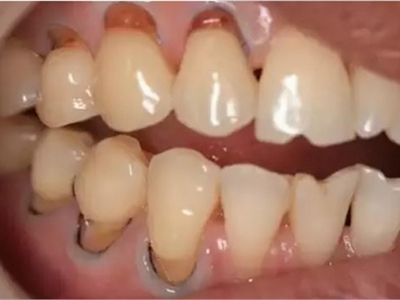

牙龈退缩上排多颗牙的牙根暴露图

牙龈退缩导致上排多颗牙齿的牙龈回缩,部分牙根暴露在外,伴有牙齿松动、口臭等症状,是由于牙周炎、局部受力过大等因素导致。